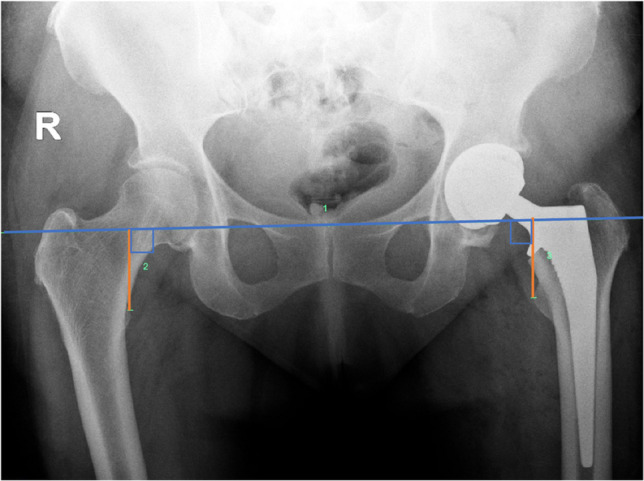

Objective: To compare the magnitude of post-arthroplasty leg length discrepancy (LLD) and incidence of clinically significant LLD measured on CT scanogram using a commonly used measurement method (from the acetabular apex to tibial plafond) to an alternative technique avoiding the use of the acetabular prosthesis as a landmark and to assess inter-observer and intra-rater reliability of the new technique.

Materials and methods: In this retrospective study, post-arthroplasty LLD measurements were conducted in 100 hips by two interpreters on CT scanogram scout views from the acetabular apex to the tibial plafond (AA-TP) and the inter-teardrop line to the tibial plafond (IT-TP). Aggregate means and proportions of clinically relevant LLD (≥ 10 mm) were compared between methods. Inter-rater reliability was calculated, and both interpreters repeated measurements on ten randomly selected patients to calculate intra-rater reliability.

Results: The commonly used AA-TP technique overestimated LLD by 3.7 mm compared to the IT-TP technique. The odds of LLD measurement exceeding the clinically significant threshold of 10 mm were 3.8 times higher when using the AA-TP technique. Excellent inter-rater (ICC 0.984, 0.958) and intra-rater reliability (ICC > 0.9) were found for both techniques.

Conclusion: CT scanogram measurements from the acetabular apex to the tibial plafond often overestimate operative limb length due to reference landmarks in different axial planes. Measurements from the inter-teardrop line to the tibial plafond yield significantly lower LLD values, possibly reflecting actual limb length better. The authors recommend using the inter-teardrop line and tibial plafond as reference landmarks to improve LLD assessment accuracy post-arthroplasty.